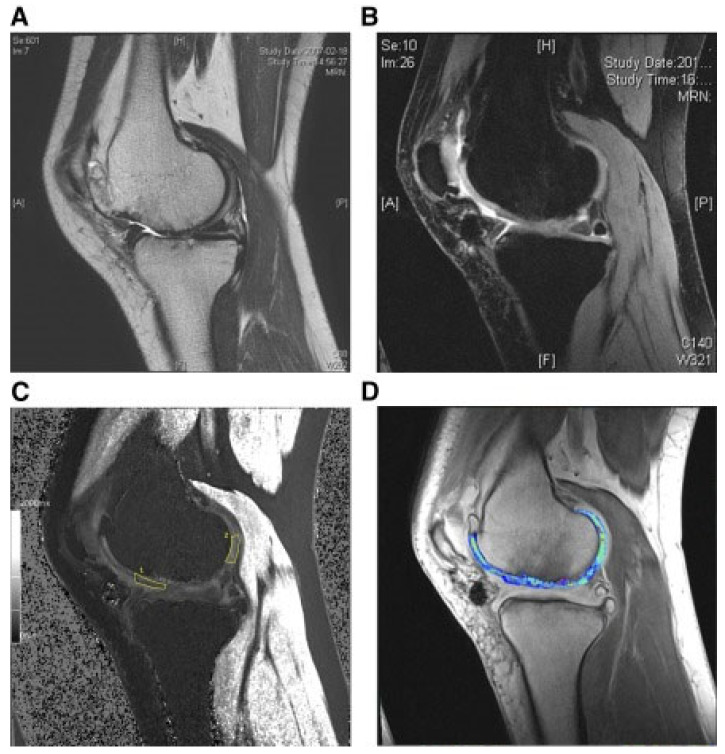

人臍帶血來(lái)源的間充質(zhì)干細胞治療關(guān)節炎

還評估了人臍帶血來(lái)源的間充質(zhì)干細胞(HUCB-MSC)治療軟骨再生的安全性和有效性。根據國際軟骨修復協(xié)會(huì )的數據,HUCB-MSC用于治療7名患有KLIII級OA和IV級軟骨缺損的患者。同種異體HUCB-MSC在體外生長(cháng),然后與HA水凝膠結合并應用于損傷部位。微骨折方案與這些細胞結合使用。12周后,修復的組織似乎成熟,24周后,臨床評分增加。在整個(gè)7年隨訪(fǎng)過(guò)程中,臨床改善的穩定性也值得注意。組織學(xué)用于在手術(shù)后一年顯示透明軟骨,而MRI用于在手術(shù)后3年顯示軟骨再生,如圖所示圖3(其中釓-DTPA用作造影劑,以藍色顯示)。

圖3:HUCB-MSC治療后3年軟骨再生的MRI評估

(A) 術(shù)前軟骨缺損。(B) 移植后3年軟骨再生。(C) 通過(guò)在標記區域采樣來(lái)計算相對軟骨松弛率的變化。(D) 顯示與藍色信號相關(guān)的GAG含量增加。

在7年的隨訪(fǎng)期間,沒(méi)有發(fā)現惡性腫瘤病例,只有5名患者出現中度至重度治療相關(guān)不良事件。